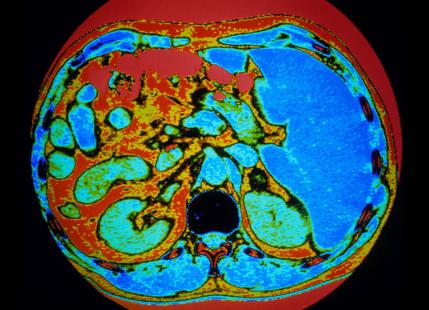

D’importantes avancées ont eu lieu ces derniers mois sur les tumeurs corticosurrénaliénnes, bégnines et malignes, avec la découverte d’une étiologie précise pour les hyperplasies macronodulaires bilatérales des surrénales, un démembrement moléculaire des corticosurrénalomes malins et la découverte d’une mutation activatrice de la PKA. Les tumeurs hypophysaires, elles, bénéficient de l’arrivée du pasiréotide, quand, dans le cancer thyroïdien, on pourrait éviter le traitement inutile d’un cancer sur trois si la décroissance thérapeutique est validée.